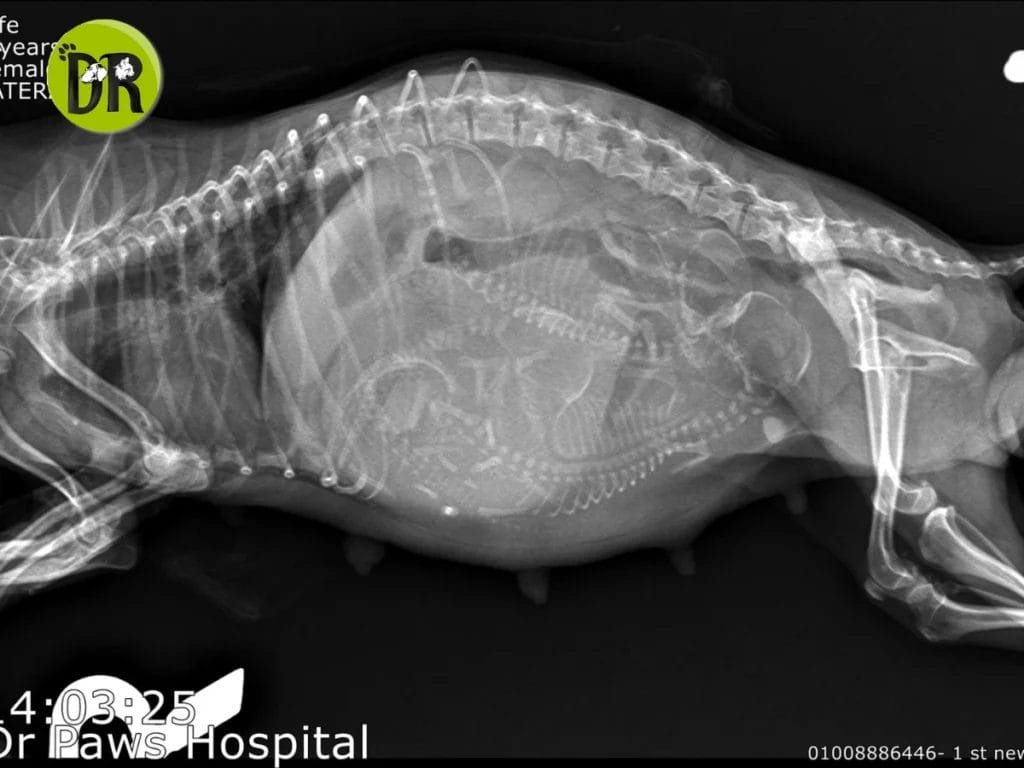

التخدير الآمن في العمليات القيصرية – من خدماتنا المميزة في عيادتنا بالتجمع الأول

في عيادتنا، نهتم بأدق التفاصيل التي تحفظ حياة حيوانك الأليف، خصوصًا في المواقف الحساسة مثل العمليات القيصرية كما عرضناه لكم عبر صفحتنا على لينكدإن.

هذه الجراحة لا تتعلق بحياة الأم فقط، بل بحياة صغارها أيضًا

لذلك حرصنا على تطبيق أحدث بروتوكولات التخدير العالمية في مثل هذه العمليات، والتي تشمل:

- قبل العملية يتم إجراء تحاليل دم كاملة ووظائف كبد وكلى لتفادي أي مضاعفات.

- يتم تزويد الأم بالأكسجين مسبقًا لضمان وصوله لها ولأجنّتها.

- نستخدم أدوية تخدير آمنة بجرعات محسوبة بعناية، مع متابعة مستمرة لمعدل التنفس وضربات القلب وضغط الدم.

- كما يتم إعطاء السوائل المناسبة خلال العملية للحفاظ على استقرار الجسم.

بفضل خبرة Dr. Ahmed Mohamed Abd Elhafiz وفريقنا الطبي، نوفر بيئة آمنة للأم وصغارها، مع تقليل المخاطر وتحقيق أفضل نتائج خلال الجراحة وبعدها.

هذه الخدمة جزء من مجموعة خدماتنا الطبية والوقائية والتجميلية في عيادتنا بالتجمع الأول، حيث نحرص دائمًا على أن يكون حيوانك الأليف في أيدٍ أمينة.ة.